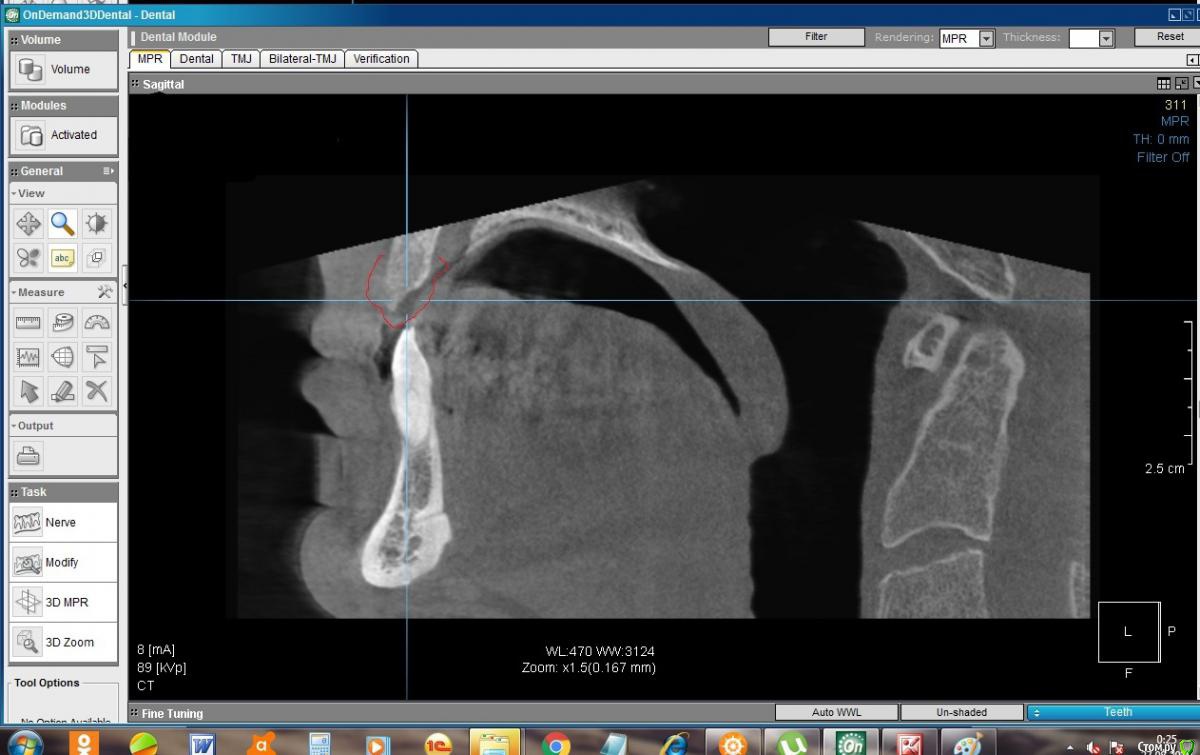

konst2009 Опубликовано 26 августа, 2019 Поделиться Опубликовано 26 августа, 2019 Здравствуйте.Два с половиной месяца назад удалил верхние передние 4 зуба. Вчера сделал KT. В сагиттальной проекции на месте лунок удаленных зубов вместо ожидаемой костной ткани как будто пустота, где-то даже губная пластина не просматривается. Срезы между лунками: Такое разве пригодно для имплантации? Что делать, ждать? Ссылка на комментарий

konst2009 Опубликовано 27 августа, 2019 Автор Поделиться Опубликовано 27 августа, 2019 Здравствуйте! После удаления зуба,объём костной ткани неминуемо уменьшается,чем больше времени после удаления-тем меньше костной ткани останется Понятно, но в лунках, если я правильно понимаю, после удаления сначала образовывается кровяной сгусток, а потом костная ткань, а ее почему-то на КТ не видно, как будто там пустота, как это можно объяснить? Ссылка на комментарий

колесников Опубликовано 27 августа, 2019 Поделиться Опубликовано 27 августа, 2019 Слабоминерализованая,потому не контрастируется Ссылка на комментарий